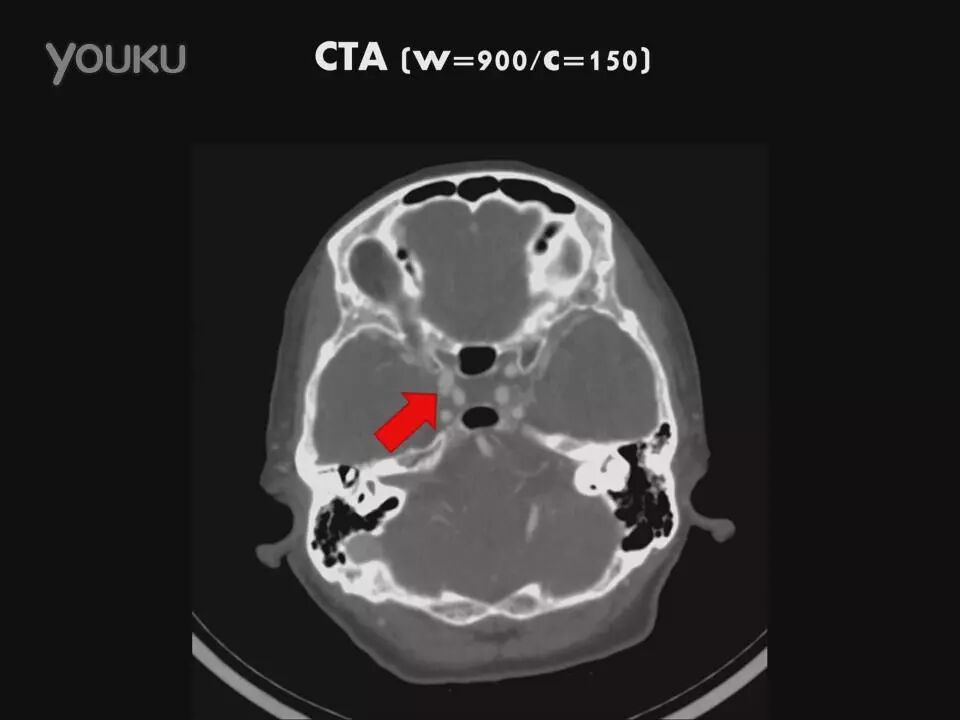

许秉权教授:显微手术钳夹海绵窦内动脉瘤